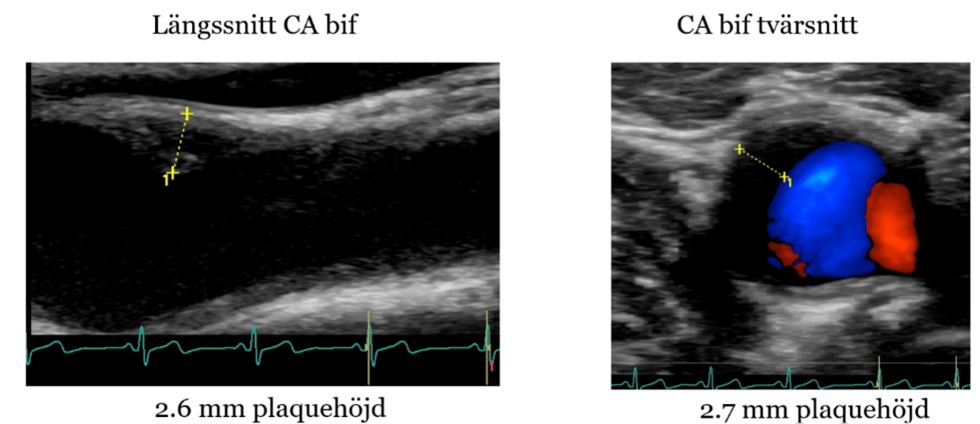

Bilder visar plackbildning.

På vilket sätt kan bedömningen underlättas?

Underlättas genom doppler med färgsättning